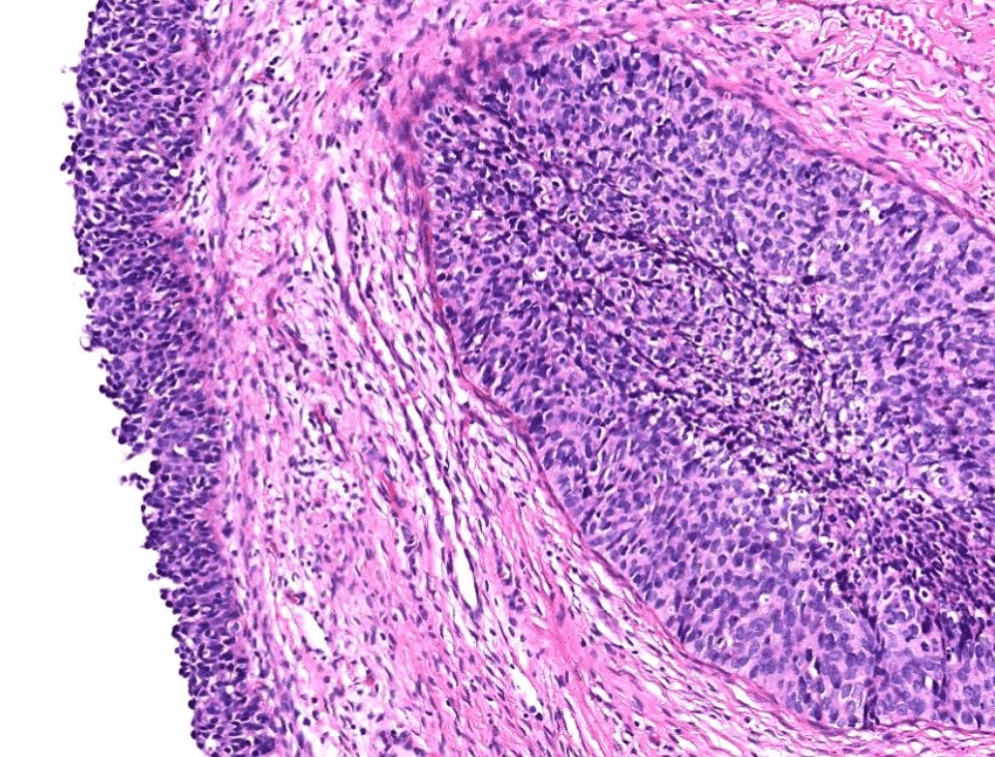

lung adenocarcinoma